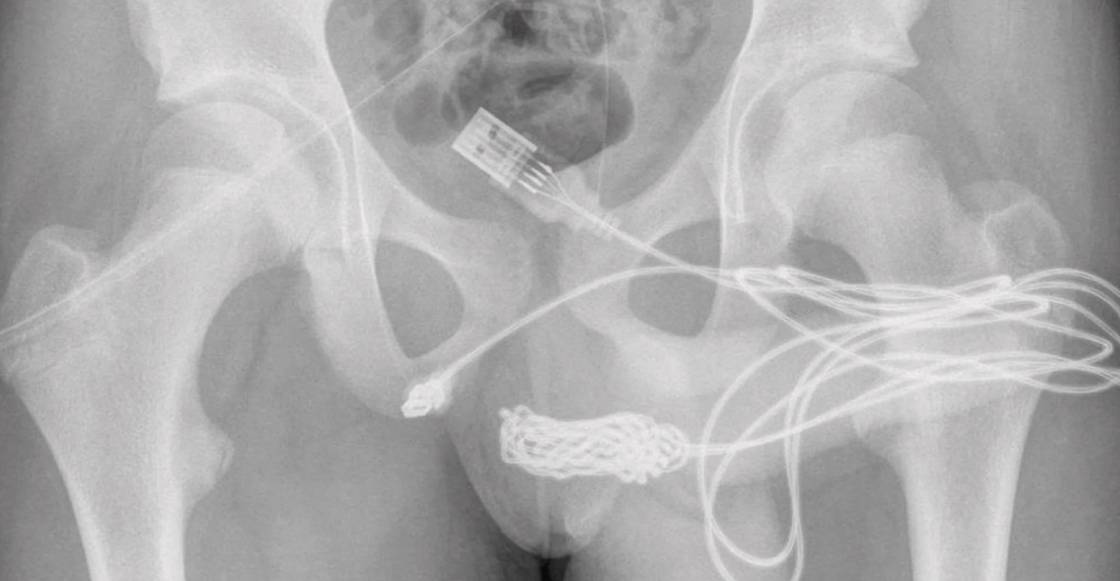

Una radiografía tomada en el hospital muestra el cable USB dentro del cuerpo de este jovencito. De acuerdo con la revista médica Urology Case, los cirujanos encargados de la operación tuvieron que hacer una incisión entre sus genitales y ano para sacar el cable. Al final la intervención fue un éxito y el chico fue dado de alta al día siguiente con analgésicos, antibióticos y catéteres uretrales.